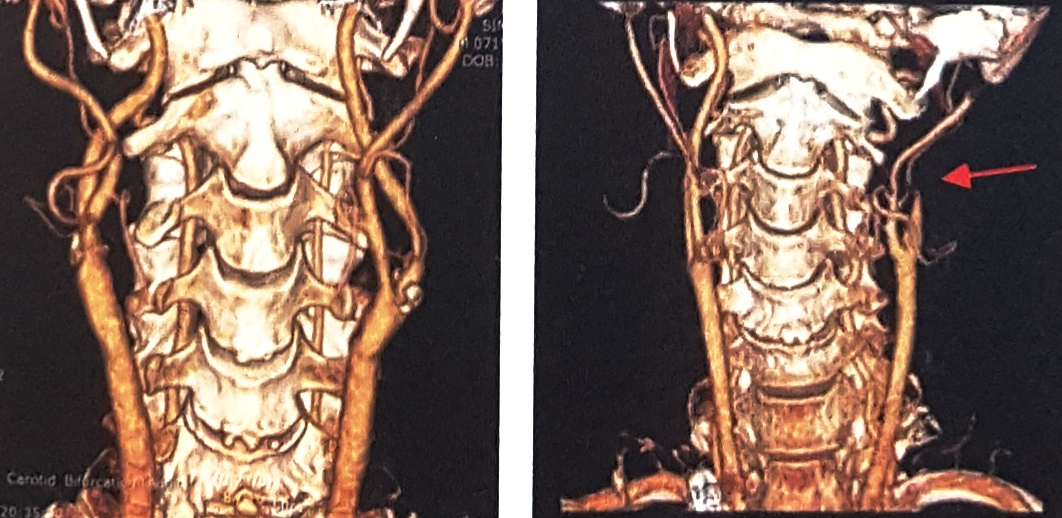

CT(Computed Tomography, 전산화단층촬영)검사는 신체의 일정 원하는 부위에서 단면을 깨끗한 2차원 영상으로 볼 수 있는 검사입니다. 촬영이 끝난 후 이러한 2차 단면영상을 컴퓨터를 이용하여 삼차원(3D)영상으로 재구성하면 동맥이 특별히 잘 보일 수 있도록 입체적인 영상도 얻을 수 있습니다.

목에 있는 경동맥